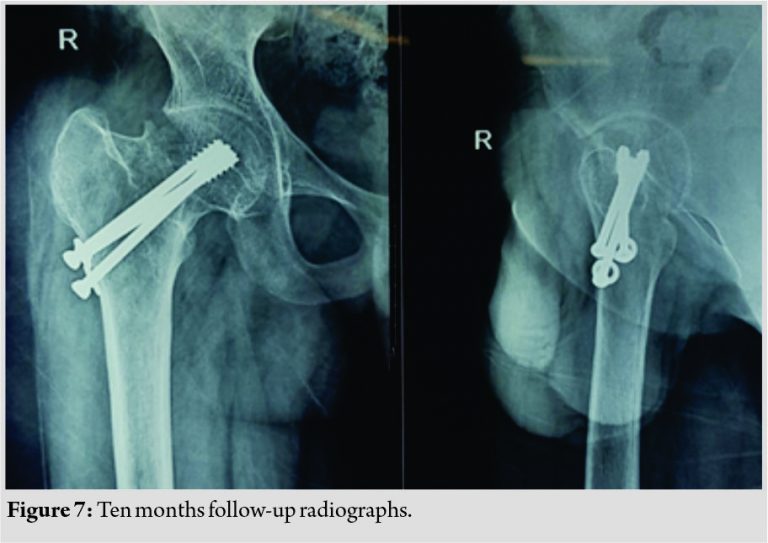

Post-operative radiograph showed good reduction on both views (Fig. 3). Post-operative period was uneventful. The patient was started on non-weight-bearing mobilization on the 2nd post-operative day. There were no complications. Range of movement exercises of the knee was started as the patient had arthrofibrosis of the right knee due to prolonged splinting. At the end of 6 weeks, the patient was started on partial weight-bearing as tolerated and then gently on full weight-bearing. He was also started on physiotherapy in the form of hip and back strengthening exercises at the end of 6 weeks. The patient resumed his daily work and had not faced any challenges. The patient had shortening of 1.5 cm of the right lower limb but was manageable with a shoe rise and has never been a concern clinically. Functional assessment was done using Harris Hip Score (Fig. 4) and was recorded at 6 weeks, 3 months, 6 months, 1 year, and 15 months follow-up. Radiologic assessment was done at the time of 1 month (Fig. 5) and until 15 months to check for fracture union and to rule out AVN of femoral head and implant loosening (Fig. 6, 7).

At 15 months follow-up, Harris Hip Score was found to be 95 with excellent outcome with no restriction of movements (Fig. 8) and the fracture united completely with no evidence of AVN (Fig. 9).